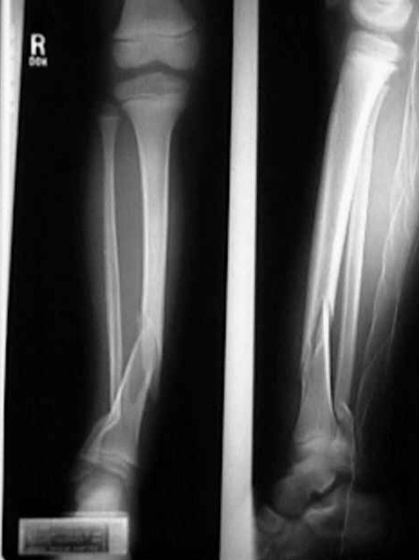

Tibia

Tibial shaft fractures are the most common lower extremity long bone fracture and typically involve a concurrent fibular fracture.

These fractures commonly occur due to high-energy trauma.

Patients with a tibial shaft fracture present with pain, swelling, and inability to bear weight.

Treatment of a tibial shaft fracture includes casting for nondisplaced fractures and intramedullary nailing if displaced or unstable.

Tibial shaft fractures are at an increased risk for developing compartment syndrome, which requires a fasciotomy to salvage the limb.